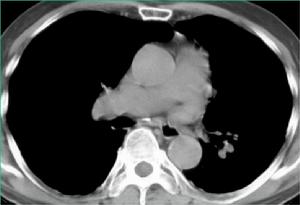

肺動脈高壓CT表現肺動脈高壓的症狀是非特異的,早期可無症狀,隨病情進展可有如下表現:

3.胸片:提示肺動脈高壓的徵象有:右下肺動脈橫徑≥15mm,肺動脈段突出≥3mm,中央肺動脈擴張、外周肺血管丟失形成“殘根征”,右房、右室擴大,心胸比增大。

7.高解析度CT和增強CT:提供更詳細的肺實質和肺血管影像學信息。